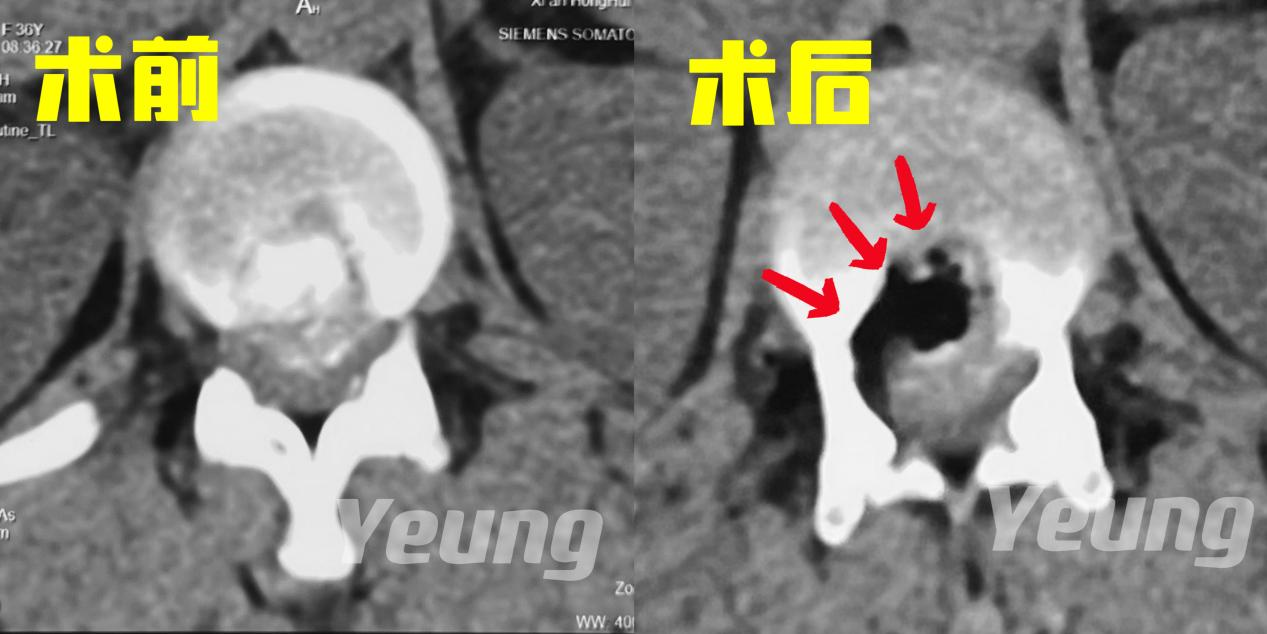

CT显示:间盘突出&钙化严重

手术中,杨俊松副主任医师在术中影像科的密切配合下采用S8导航进行了实时的操作导引,给手术插上了“透视眼”。为增加手术安全性,采用超声骨刀仔细去除钙化物,给受压的脊髓神经减压,影像显示减压彻底。

手术前后影像资料对比

本例患者术前双侧均有症状,内镜下单侧入路手术后双侧症状均缓解,且出血少,贫血患者更安全,恢复快。患者术后行走,笑容满面。